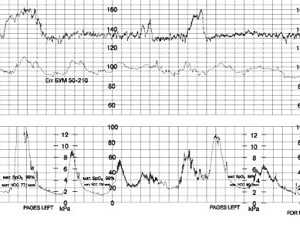

Пульсоксиметрия плода - определение кислородной насыщенности крови. Выявляет снижение сатурации кислорода;

Кардиотокограмма представляет собой бумажную ленту (движущуюся со скоростью 1-3 см/мин.) с двумя кривыми, совмещенными по времени. Одна из них (верхняя кривая) отображает частоту сердечных сокращений (ЧСС), а другая ― маточную активность (сокращение матки).

Тахограмма - это исследование регистрирует изменение сердечных сокращений плода во времени. График показывает время исследования в минутах и частоту сердечных сокращений в минуту. Если происходит повышение частоты сердечных сокращений плода, то кривая идет вверх, если частота сердечных сокращений падает - кривая идет вниз.